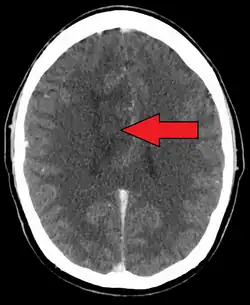

| A oligoastrocytoma on CT | |

An X-ray computed tomography (CT) or magnetic resonance imaging (MRI) scan is necessary to characterize the anatomy of this tumor as to size, location, and its homogeneity and heterogeneity. However, final diagnosis of this tumor, like most tumors, relies on histopathologic examination (biopsy examination).[4]